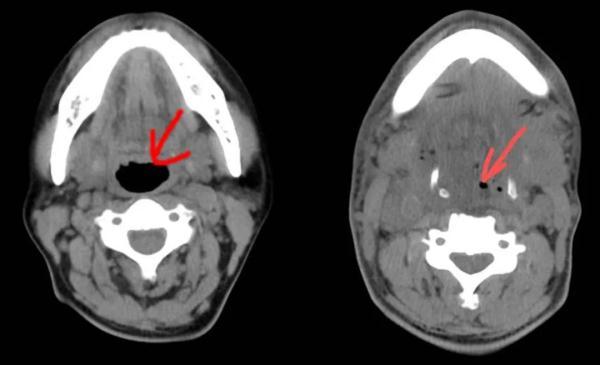

急診CT影像片子里,蔣先生的咽喉、口底、頜下等部位有大量積液和積氣,氣管已被擠得“消失”。

蔣先生的病情一天天好轉(zhuǎn),術(shù)后第五天的CT影像片子里,終于出現(xiàn)了氣管的蹤跡,雖然只有黑豆那么大。能自主呼吸,意味著能拔氣切插管了。

左圖為正常氣管,右圖為患者術(shù)后第五天的氣管